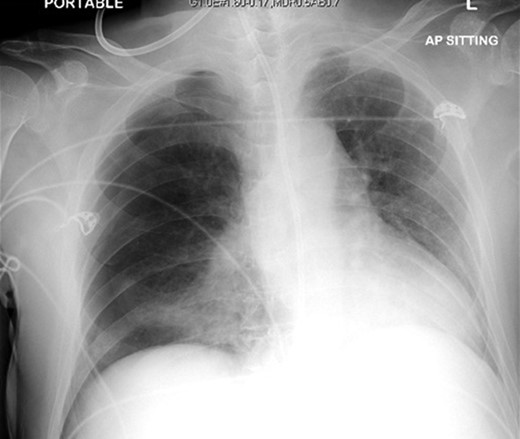

The patient was urgently reviewed by the cardiothoracic surgeons, and a small-bore chest tube was inserted, following which a computed tomography of the thorax was performed. This showed a residual but smaller pneumothorax with the chest tube in situ, associated with a small hemothorax (Fig. 3). Due to failure of conservative management and concern of a bronchopleural fistula resulting in air leak, he underwent explorative thoracoscopic surgery. Intraoperatively, an area of lung was noted with contusional changes and a bleb (Fig. 4), and a wedge resection of the right lower lobe was performed (Fig. 5). He made an uneventful recovery and was discharged.

Representative axial slice of computed tomography thorax showing a residual but smaller pneumothorax with the chest tube in situ.